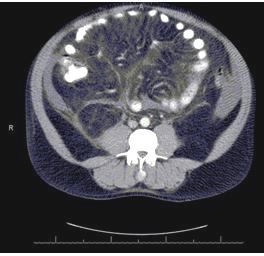

The patient was admitted for workup of abdominal pain and evaluation of ascites and bilateral pleural effusions noted on CT scan (Figure 1, left). There were no radiological findings of ischemic colitis, portal hypertension, hepatic vein thrombosis, or mesenteric ischemia. A complete blood cell count initially showed a hemoglobin level of 10.8 g/dL (normal range, 14-18 g/dL), a platelet count of 593,000/µL (normal range, 150,000-400,000/µL), and a normal white blood cell count of 91,000/µL, with eosinophilia (2300 cells/µL; normal <350 cells/µL); during the hospital course, the eosinophil count was as high as 4500/µL. Results of an iron panel were consistent with anemia of chronic disease. A comprehensive metabolic panel revealed BUN of 23 mg/dL (normal range, 8-23 mg/dL) and creatinine of 1.2 mg/dL (normal range, 0.6-1.2 mg/dL), with normal liver function. Erythrocyte sedimentation rate was elevated at 69 mm/h (normal range, 0-20 mm/h).